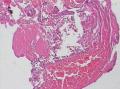

气管镜活检

性别年龄60临床诊断肺结核

标本名称气管镜活检

• 气管镜活检图1

图1

考虑炎性病变,结核可能?

考虑鳞癌,进一步检查。

支气管粘膜炎症,伴有出血、渗出、坏死及少许肉芽组织,诊断结核证据不足!

考虑炎症

炎性病变

出血及坏死,有肉芽性炎,结核还是要考虑的,多做些工作,逐一排除

出血及坏死,有肉芽性炎,结核还是要考虑的,多做些工作,逐一排除,首先考虑结核。